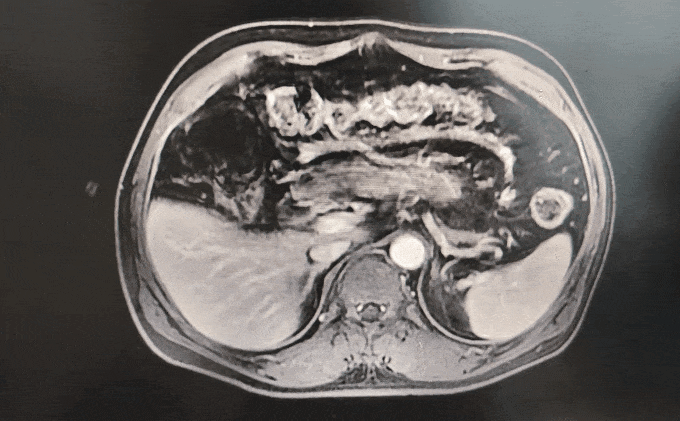

◈ 2022-8-10 胸腹盆增强CT提示:胰腺体部强化减低并胰管局限性稍扩张,肠系膜上动脉、腹腔干近段及局部分支软组织影包绕,考虑患者胰腺占位诊断明确(占位大小无法准确评估),但需鉴别恶性肿瘤及免疫相关疾病。

2022-8-10 胸腹盆增强CT